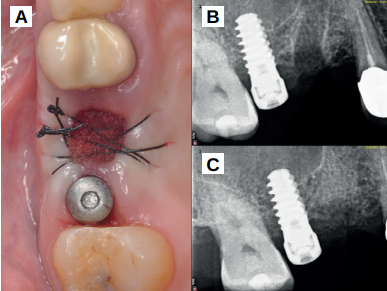

Caso clínico: se presenta el caso clínico de una mujer de 61 años, que acudió a consulta presentando dolor intenso en la zona del segundo premolar superior derecho (1.5). Se realizó la exodoncia del 1.5, usándose como diente donante para realizar una preservación del alveolo tras la extracción. Cuatro meses tras el procedimiento, se colocó un implante y se tomó una biopsia para realizar un análisis histomorfométrico. Un año tras la carga del implante se observaron buenos resultados clínicos y radiográficos.

Clinical case: a 61-year-old woman is presented, who came to private dental clinic presenting intense pain in the area of an upper bicuspid of the first quadrant (1.5). Exodontia of the 1.5 was performed, using it as a donor tooth to obtain the biomaterial to preserve its alveolus. After 4 months re-entry was performed and an implant was placed, harvesting a bone biopsy for histomorphometric analysis. One year post-loading, good clinical and radiographic results were shown.